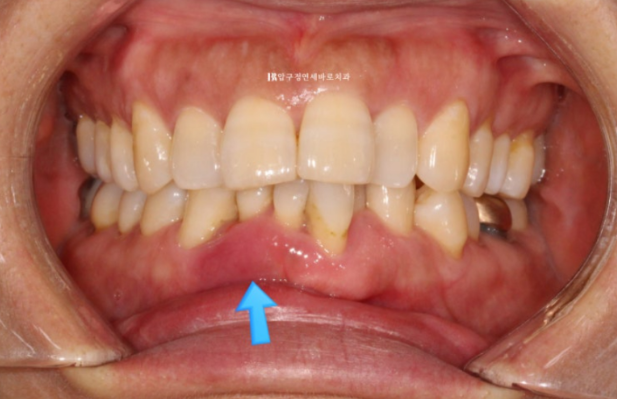

파란 화살표 부위가 치주염이 심한 부위입니다.

앞니 4개 중 3개가 모두 흔들리며 치주염이 깊은 상태여서 발치가 불가피한 상황입니다.

3개 중 2개는 발치를 하고 나머지 1개는 많이 흔들리지만 쓸때까지 쓰다가 나중에 빠지면 보철을 하기로 정하고 교정치료를 했습니다.